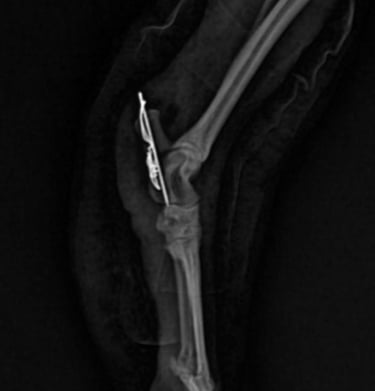

Cirurgias

Procedimentos realizados com precisão para recuperação eficaz.